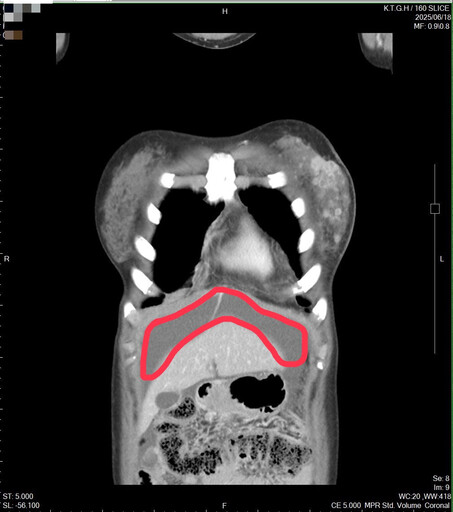

2025年3月,癌症再次復發,甚至已經出現腹積水。

不過在2025年3月,癌症再次復發,甚至已經出現腹積水。且醫療團隊進一步檢查後發現,林小姐的癌細胞特徵有所變化,從原本的HER2陰性轉為HER2低表現(由0分變為2+,代表介於陰性與陽性之間),使其需接受新一代標靶治療。廖志斌醫師表示,這顯示乳癌是一種會隨著時間與治療而改變的疾病,並非一成不變,患者若出現復發或轉移,應再次接受檢測,以便調整治療方向。